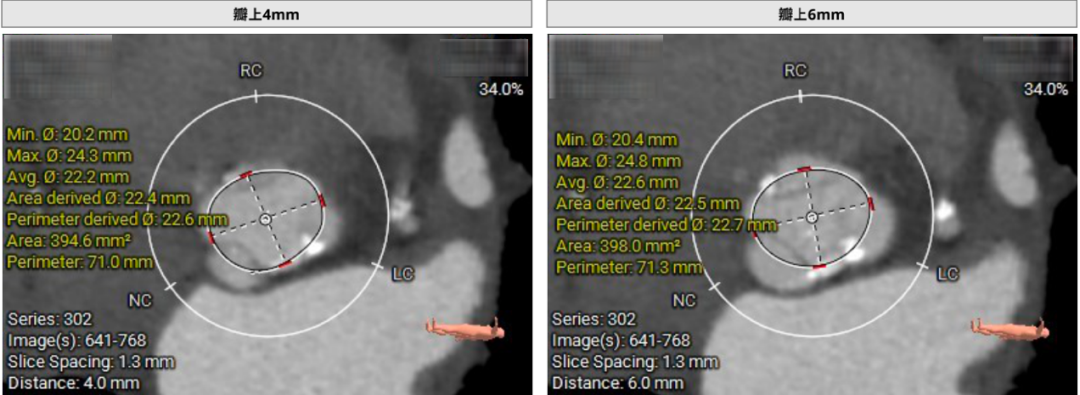

主动脉根部CTA

瓣环周长72.1mm,平均径22.9mm,LVOT周长75.6mm,平均径24.1mm。股动脉入路迂曲,分叉高度可。髂总、腹主动脉团块钙化分布。左侧血管平均最小内径7.2mm,右侧血管平均最小内径6.5mm。左冠高度低,瓣叶长,窦宽相对瓣膜可。右冠高度可,瓣叶长度可,窦宽相对瓣膜可。